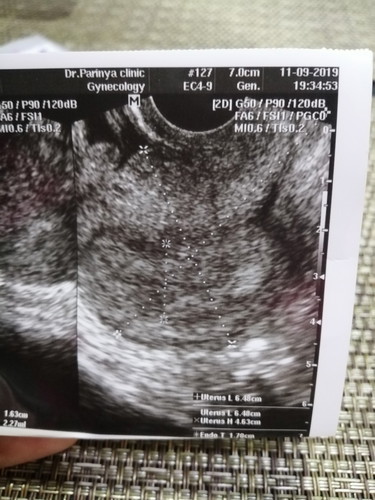

ไปให้คุณหมอซาวผ่านช่องคลอด ยังไม่พบถุงตั้งครรภ์ เจอเพียงแค่โพรงมดลูกหนาตัวขึ้น แบบนี้ปกติมั้ยคะ